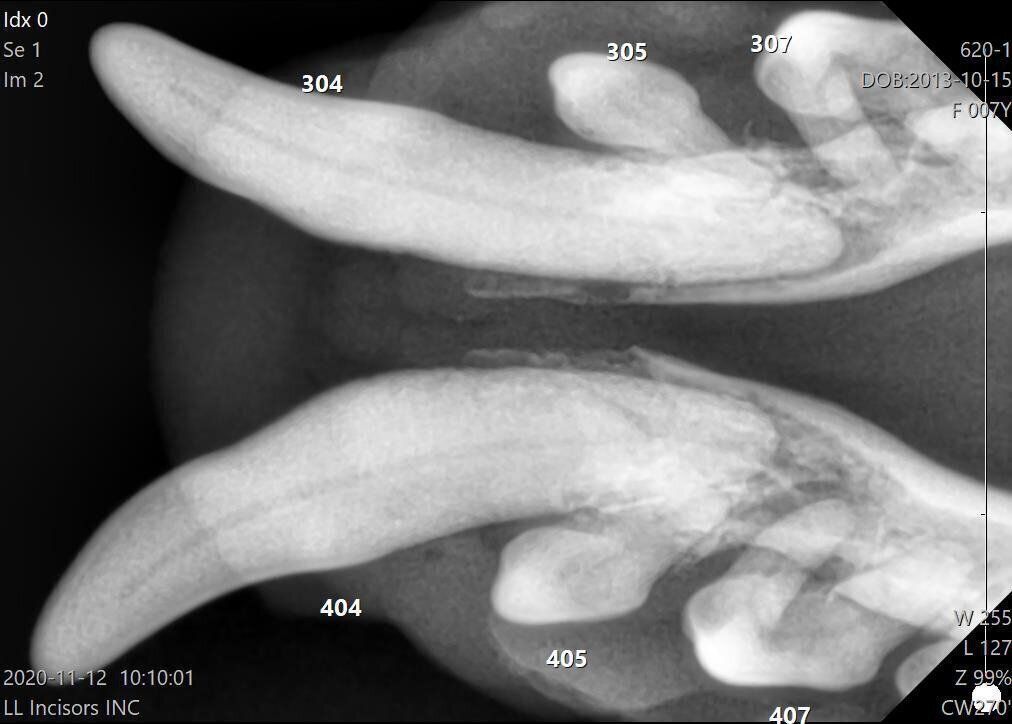

上の写真の犬の歯を、エックス線写真で撮影したもの

しかし、この犬はなぜか顔が腫れていたため、動物病院を受診しました。エックス線検査をしてみると、歯の根っこに膿がたまり、下あごの骨の底付近まで骨が溶けつつあることがわかったのです。

歯も白いですし、歯ぐきの状態もきれいなピンク色で、悪くなさそうに見えますよね。